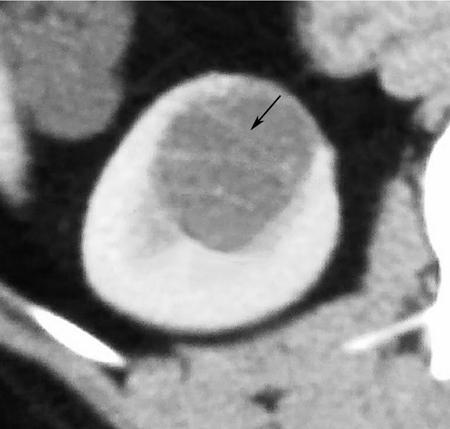

- Imaging: Bosniak type IV cysts are characterized by the presence of enhancing soft tissue nodule (Fig. 10.12.1.7).

- Risk of malignancy: They are considered malignant until proven otherwise, with risk of malignancy being 95%–100%. Very small percentage can be benign, example being MEST.

- Recommendations: Surgical resection is recommended if feasible.